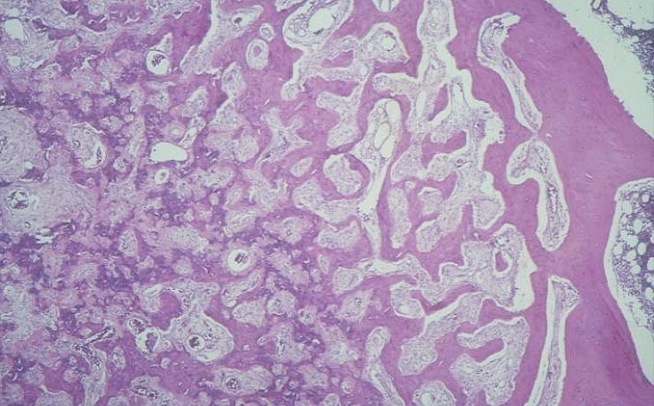

Osteosarcoma is the most common primary, malignant tumor of bone. The cancerous cells derive and from mesenchymal cells and are noted for their production of bone matrix. Osteosarcomas are associated with mutations in the retinoblastoma gene (RB) and p53. In the image, note the extensive, lace-like bone laid down by the cancerous cells. The cancerous cells vary in size and often contain very large nuclei.